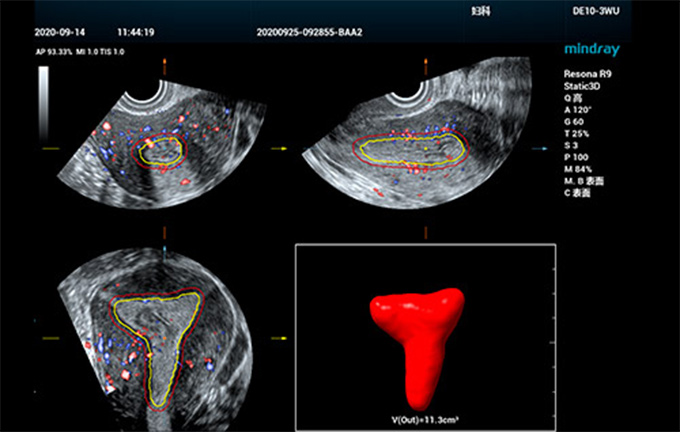

Smart ERA

A fin de mejorar la eficiencia y precisiĆ³n del diagnĆ³stico ginecolĆ³gico por ecografĆa y hacer que el diagnĆ³stico temprano de trastornos reproductivos y tumores sea mĆ”s accesible, Mindray ha desarrollado una serie de soluciones inteligentes para exĆ”menes de ecografĆa uterinos y foliculares para ayudar a los mĆ©dicos a realizar un diagnĆ³stico clĆnico eficiente. En respuesta a las necesidades de la prueba de receptividad endometrial, Smart ERA, la primera herramienta de anĆ”lisis de la receptividad endometrial completamente automatizada de la industria, desarrollada por nosotros, permite obtener imĆ”genes endometriales automĆ”ticas en 3D incluso en diferentes tipos de estructuras. Admite la mediciĆ³n automĆ”tica del volumen y el grosor del endometrio, asĆ como del Ćndice de flujo sanguĆneo endometrial. El proceso de uso simplificado mejora significativamente la consistencia del examen y la eficiencia del diagnĆ³stico, lo que permite a los ecografistas gestionar la evaluaciĆ³n previa al embarazo con mĆ”s confianza y facilidad.